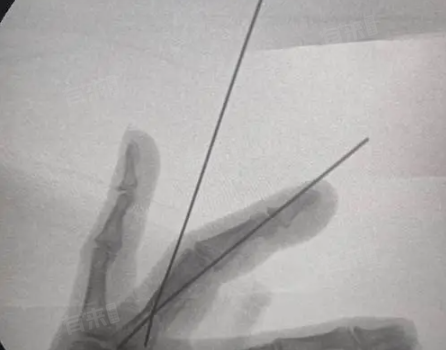

手指骨折手术后钢钉拔出的时间通常在4-14周,甚至更长,因手指骨折愈合情况、手术方式、患者个体体质、康复进度等情况不同故恢复时间有所不同。

通常情况下,如果骨折部位愈合良好,在术后4-6周可以考虑拔除钢钉,这是因为在这个时间段,骨折断端已经形成了初步的骨痂,骨头开始逐渐恢复强度,但如果X光显示骨折线仍然清晰,骨痂生长缓慢,那么钢钉就需要继续保留,可能要等到8-10周,甚至更长时间,直到骨折部位有足够稳定的骨痂形成,确保拔出钢钉后骨折不会再移位。

不同的手术方式对钢钉拔出时间也有影响,如果是简单的克氏针固定,一般在骨折达到临床愈合标准时即可拔出,大概4-6周,而若是采用了更复杂的内固定系统,如锁定钢板结合钢钉,由于固定更为牢固,钢钉的拔出时间可能会延迟到6-8周,甚至更久,这是为了保证骨折部位在复杂应力环境下也能稳定愈合。